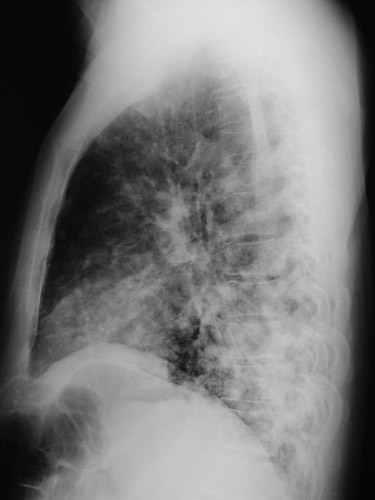

| The numerous irregular 0.5 to 1 cm nodular opacities seen here in a PA view above and lateral view below in the lung are more prominent posteriorly and inferiorly. This patient proved to have bronchiolitis obliterans with organizing pneumonia (BOOP). |